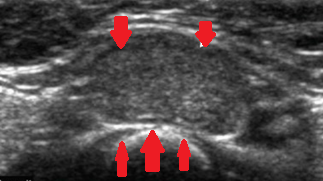

FiFigures 2,3,4 . Thyroid U/S . Encapsulated medullary microcarcinoma . (Courtesy Dr . V . Penopoulos) .